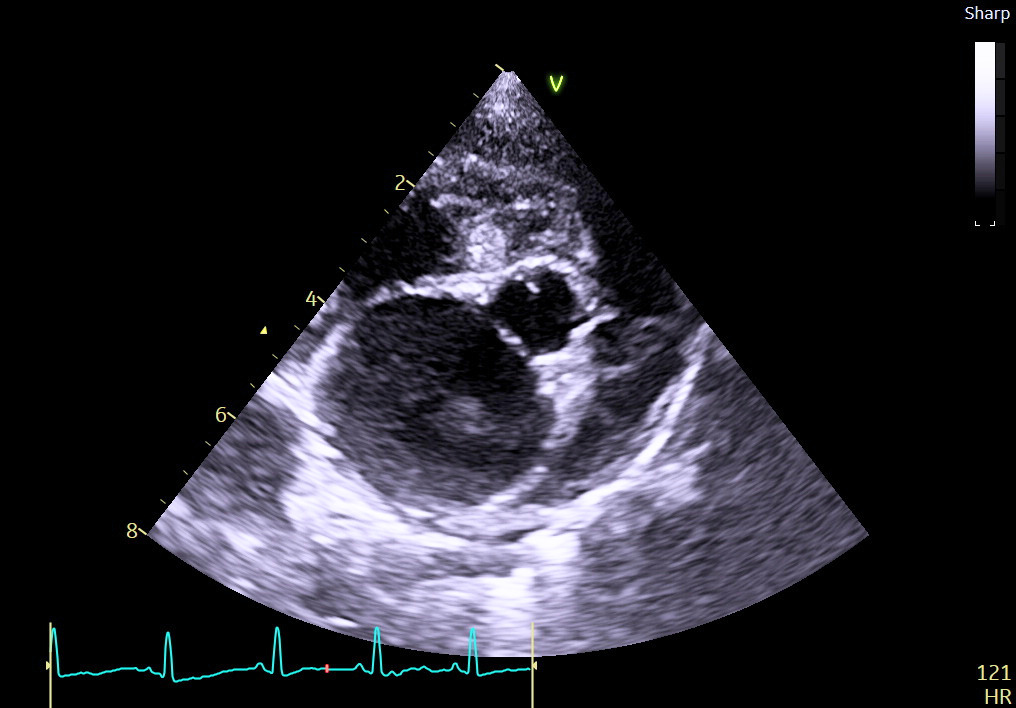

Przez lata kaszel był uznawany za jeden z kluczowych objawów obrzęku płuc pochodzenia kardiogennego u psów. Jednak współczesne badania coraz częściej podważają to klasyczne podejście, wskazując, iż interpretacja kaszlu jako objawu niewydolności serca bywa myląca i może prowadzić do błędów diagnostycznych.

Podczas spotkania przyjrzymy się krytycznie koncepcji tzw. „kaszlu sercowego”, zestawiając aktualną literaturę naukową z codzienną praktyką kliniczną.

Skupimy się na praktycznym różnicowaniu przyczyn kaszlu oraz na podejmowaniu trafnych decyzji diagnostycznych i terapeutycznych u pacjentów z chorobami serca.